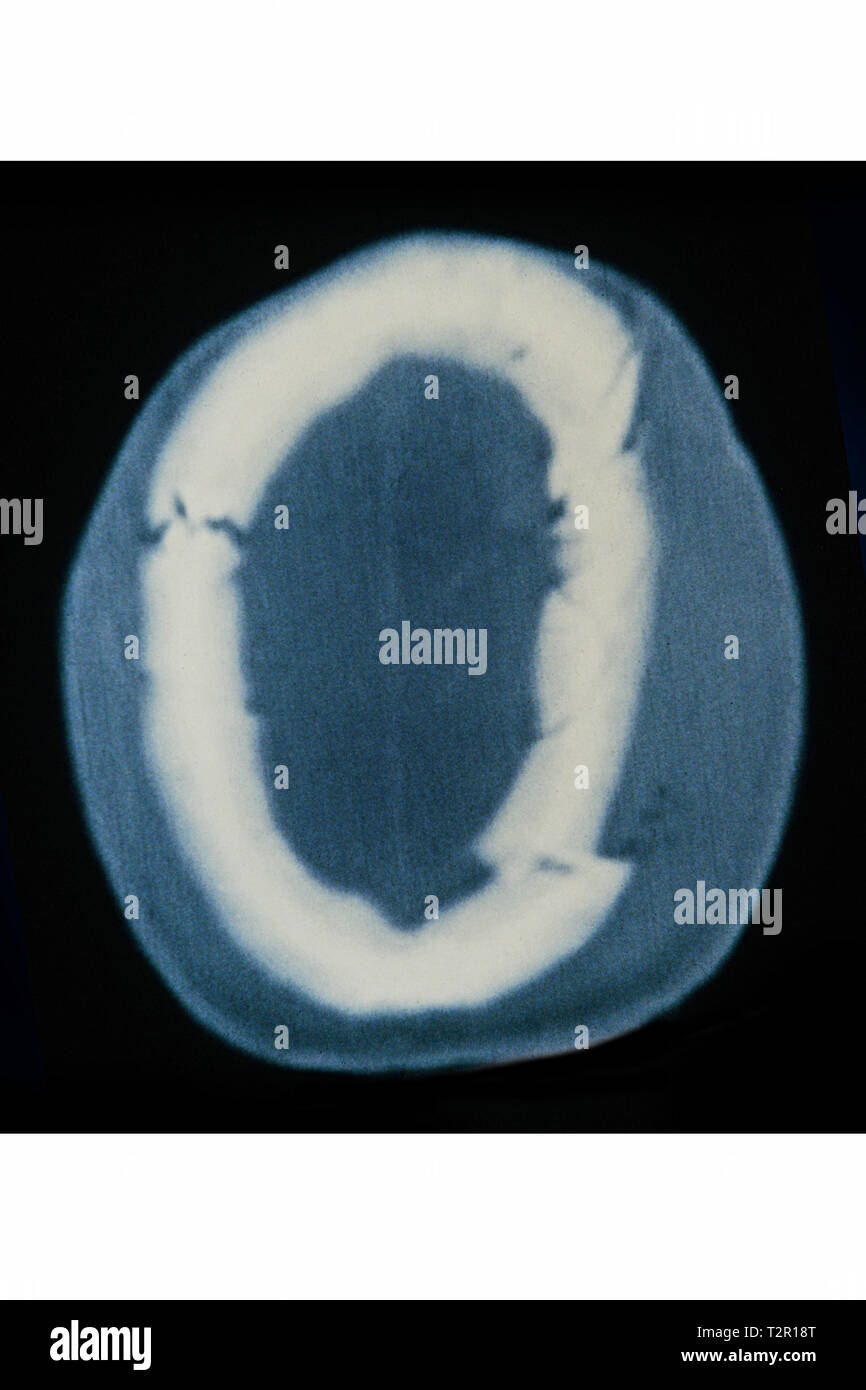

La fractura de la base del cráneo se define como una fractura ósea que afecta a alguno de los huesos situados en el suelo o base de la cavidad craneal.[1] Suele producirse por impactos importantes sobre la cabeza, por ejemplo accidentes de tráfico o caídas de altura. Constituyen el 21% del total de las fracturas de cráneo y con mucha frecuencia se asocia a otras lesiones de la cabeza como fractura de la bóveda craneal. Produce complicaciones importantes provocadas por la lesión de alguno de los nervios o vasos sanguíneos que atraviesan la base del cráneo.[2][3]

La base del cráneo está formada por el hueso etmoides, el esfenoides, las 2 porciones del hueso frontal, los 2 huesos temporales incluyendo su porción petrosa o peñasco y el hueso occipital. El conjunto se divide en tres compartimentos, la fosa craneal anterior, la fosa craneal media y la posterior. La fractura puede afectar a las tres fosas craneales, pero se localiza preferentemente en determinadas zonas que son puntos débiles de la estructura, entre ellos el techo de la órbita, la lámina cribosa del etmoides y el peñasco del hueso temporal.